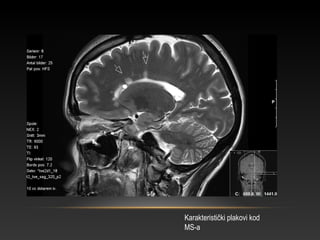

Karakteristički plakovi kod

MS-a